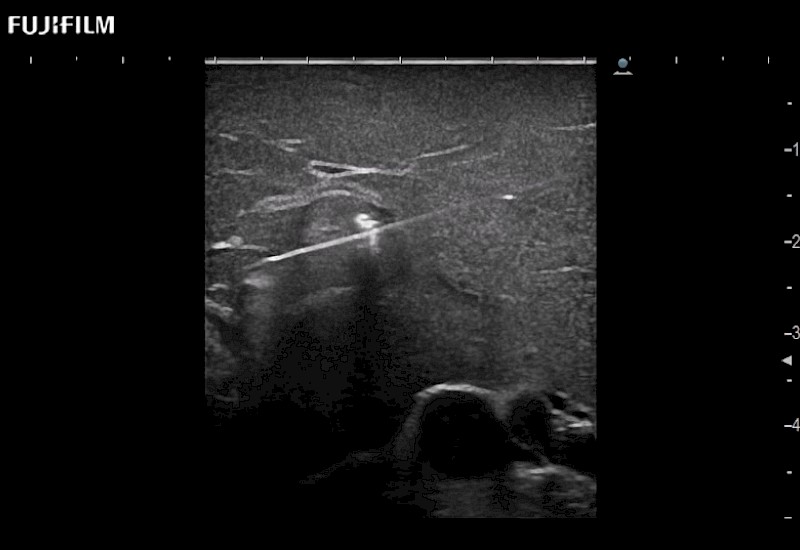

for use during general and laparoscopic procedures: Tumor localization & staging, Ablation, Resection, Biopsy, Transplant, Abdominal exploration, Robotic surgery

Our dedication to Laparoscopic Surgery allows us to offer superior image quality, outstanding system reliability and intuitive use of cutting edge technology.